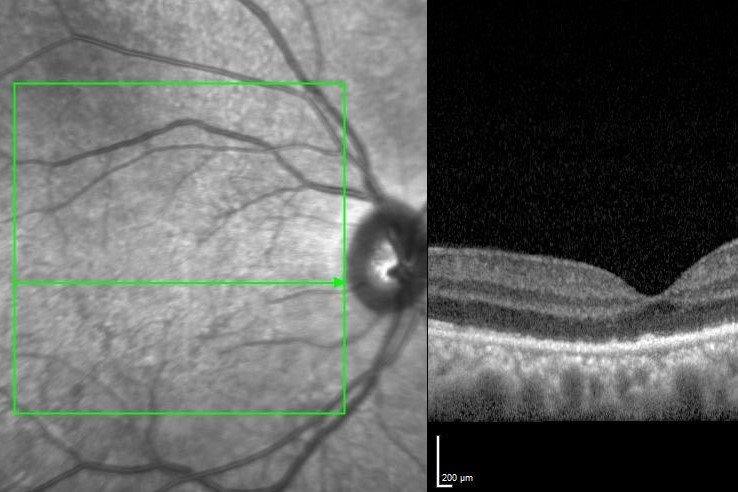

The macula in the right eye showed an indistinct pale area with some fine white mottling within. Optical coherence tomography (OCT) showed outer retinal irregularity with disruption of the ellipsoid zone and focal nodular areas of retinal pigment epithelium (RPE) thickening. There was no subretinal fluid and the OCT appearance was relatively unremarkable given the extent of vision loss (Fig 1). There was a large area of abnormal hyper-autofluorescence within the macula, correlating with the pale lesion seen, as well as a few satellite lesions (Fig 2).